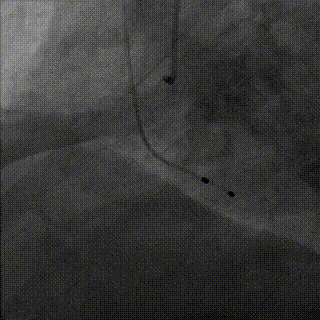

术中操作

冠脉处理前

冠脉处理后

球囊预扩

瓣膜释放

释放完成